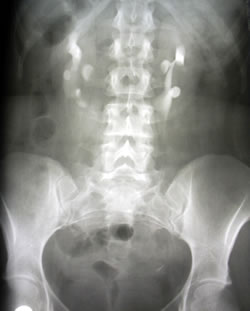

Нефроптоз 3 степени: диагностика и рентгенологические признаки